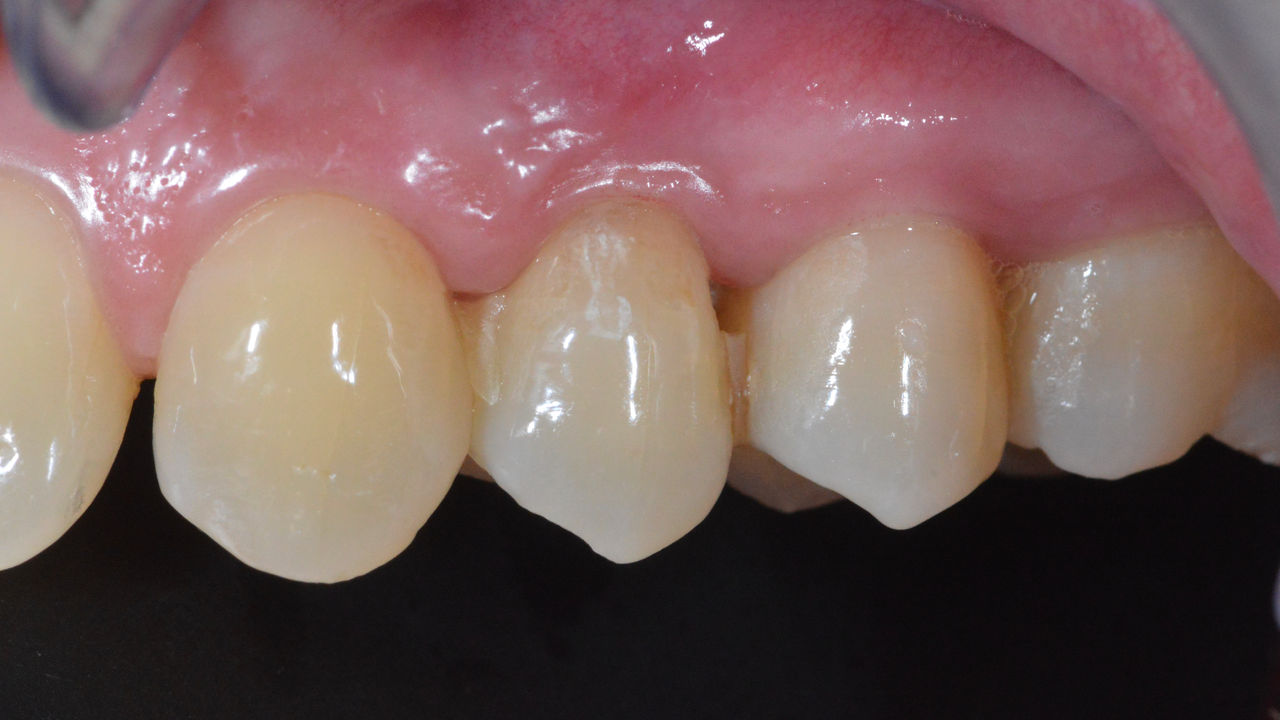

Incisivos centrales superiores en 4 horas

Cuatro coronas individuales IPS.emax CAD

La restauración con coronas de cerámica no requirió preparación subgingival para cubrir el margen y ninguna sombra de metal oscuro alteró la estética. Con CEREC Primescan y CEREC Primemill, los pacientes reciben una restauración de cerámica de alta calidad más rápido que nunca.

Antes: Obturaciones inadecuadas en los dientes 12 a 22, una línea gingival irregular en los dientes 12 y 11 y bordes incisales gravemente erosionados.

Después: Cuatro coronas de cerámica de disilicato de litio altamente estéticas e individualizadas.

Claudia Scholz

Kiel, Alemania